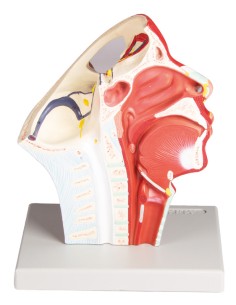

Erler Zimmer, modèle anatomique pour expliquer l'hygiène bucco-dentaire D217

Erler Zimmer, modèle anatomique pour expliquer l'hygiène bucco-dentaire D216